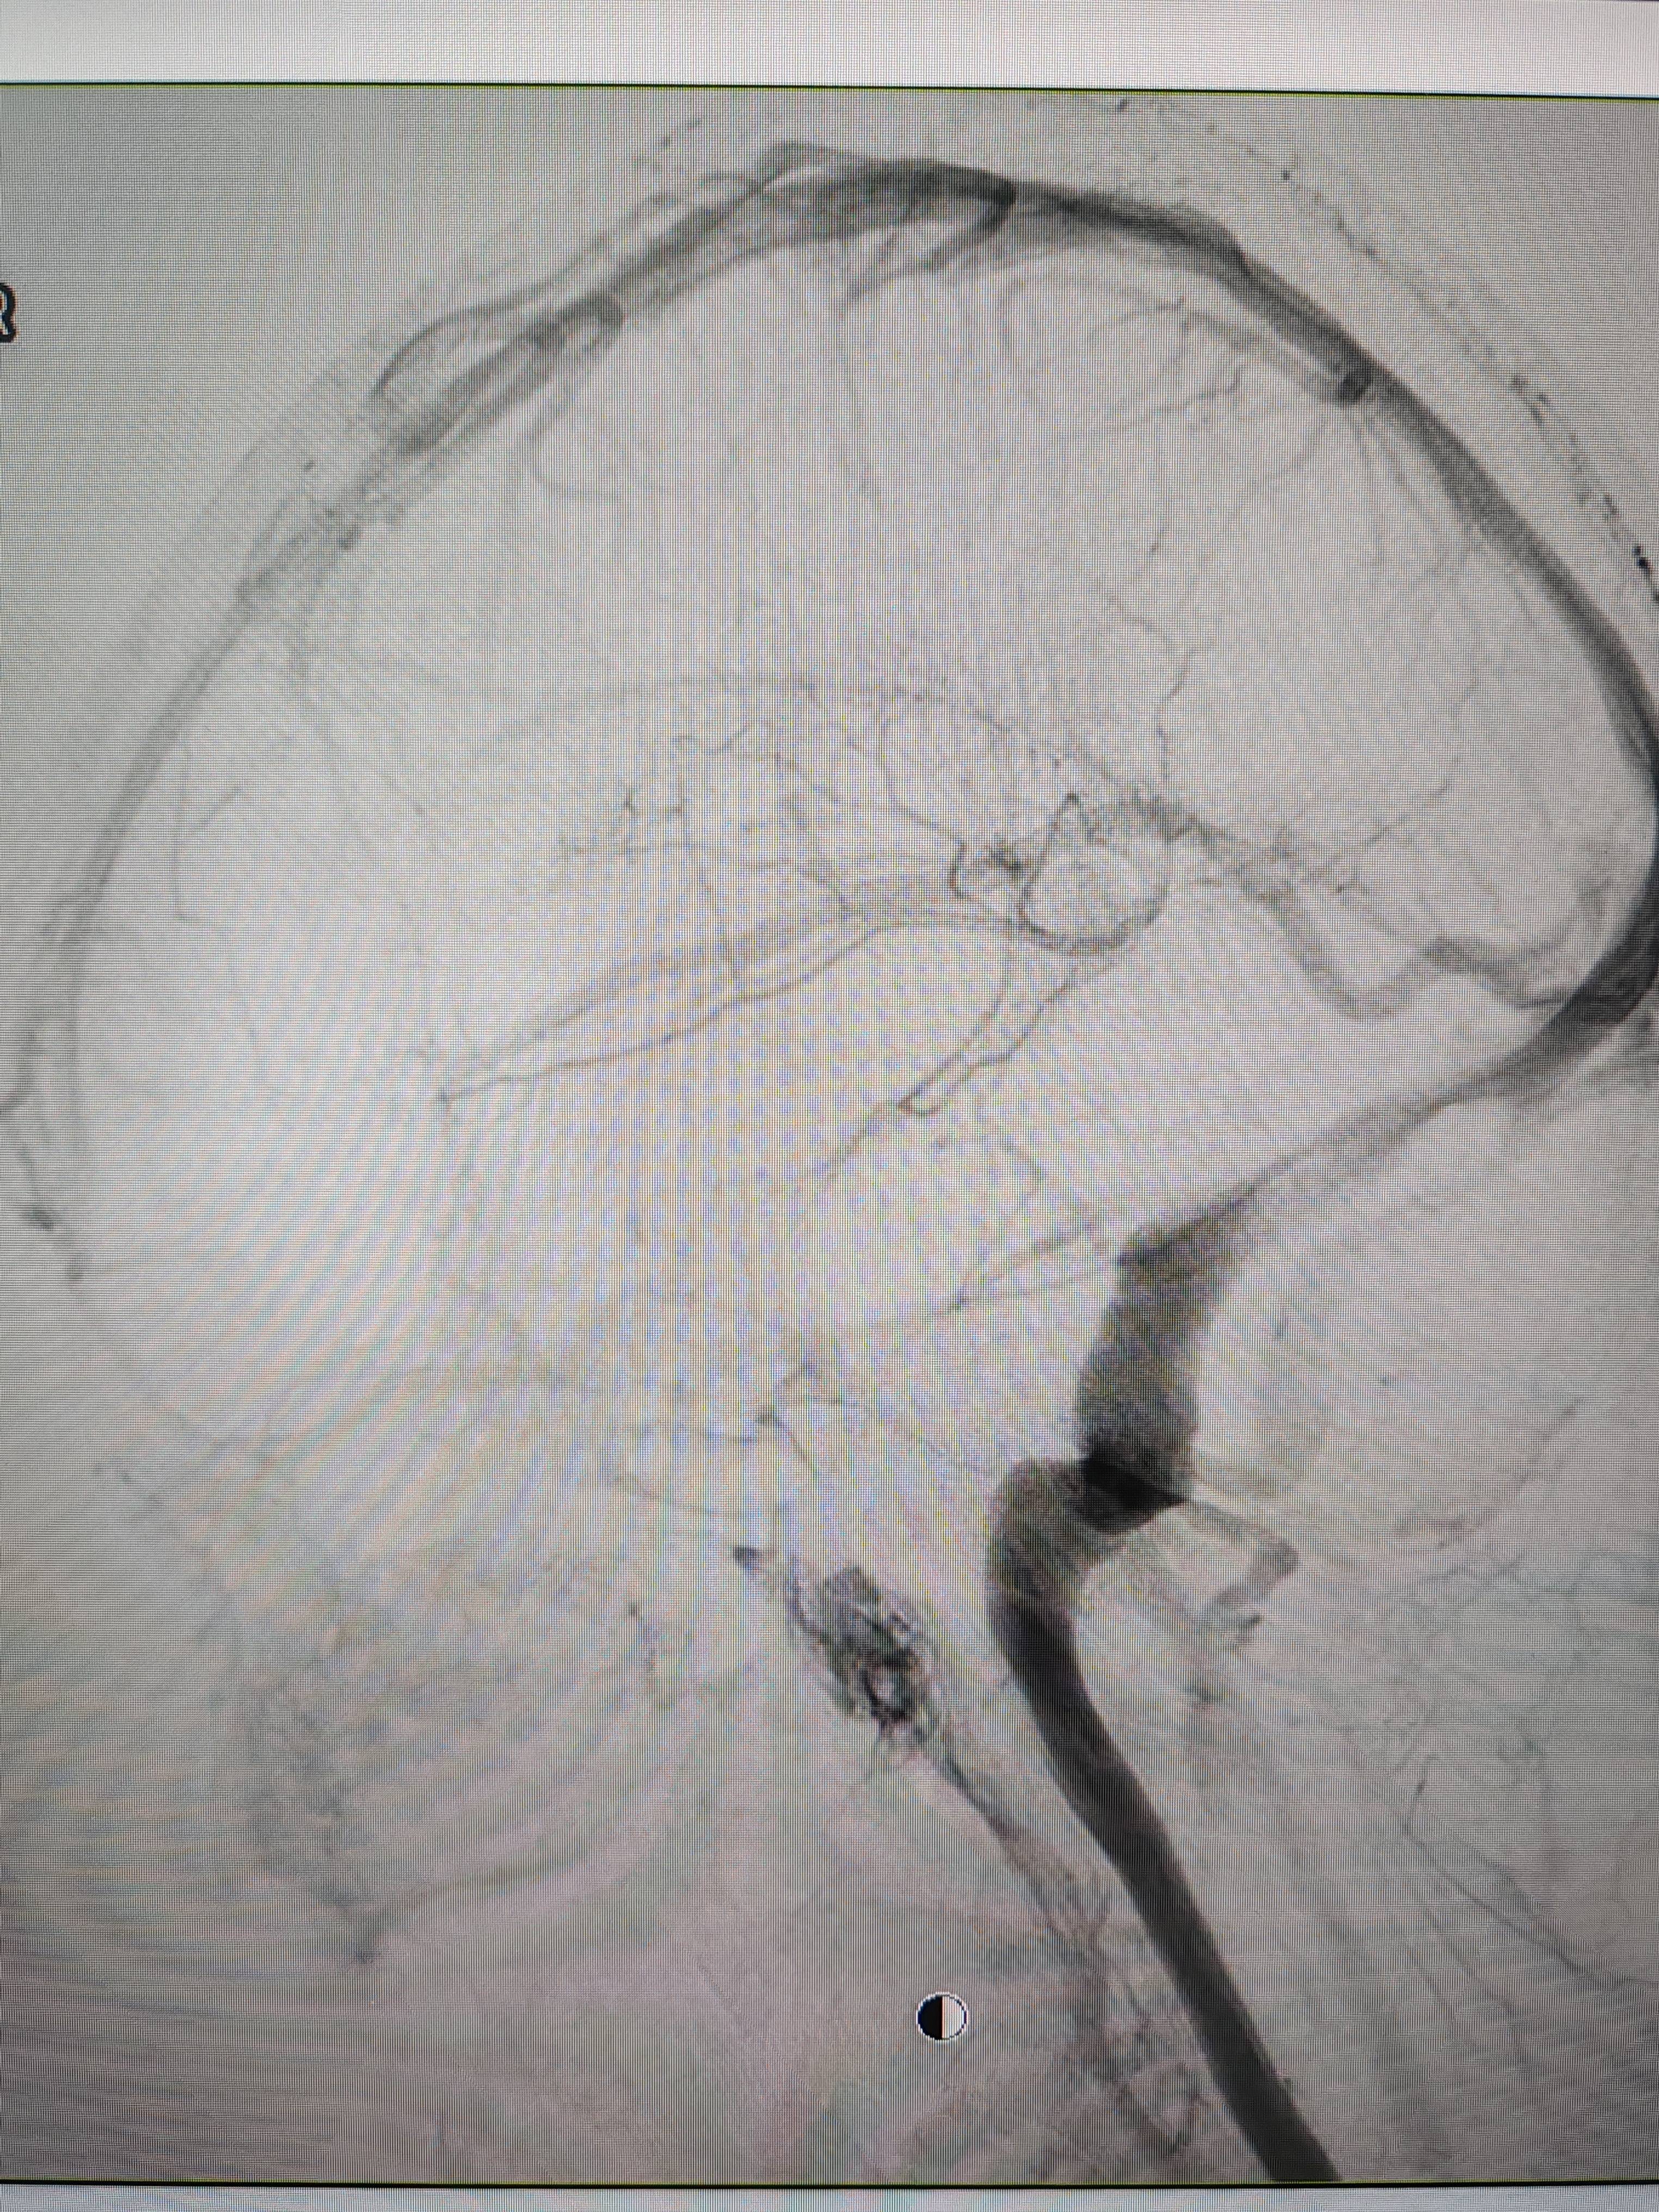

患者造影图像显示,其耳侧静脉窦狭窄BFX合约平台。 南方+ 欧阳少伟 拍摄

李宝民举例说,通过查体、CT、造影等影像技术的检查,患者赵女士是由于静脉窦狭窄,导致缓慢的静脉血流也出现“湍流”现象,其拐弯、打漩涡、回流产生的声响,又顺着骨传导,传至耳蜗处,进而让患者出现搏动性耳鸣的症状BFX合约平台。